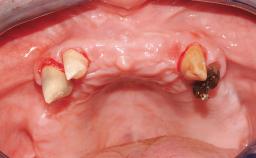

Surgical treatment of a 68-year-old female patient who experienced failure of her conventional bridge in the right maxilla. After removal of the compromised abutment teeth and a healing period of 6 weeks, a sinus floor elevation procedure using the lateral window technique and a composite graft to correct the insufficient bone height is carried out.

Two dental implants are placed in the same surgical session. The case concludes with the presentation of the final fixed dental prosthesis with a distal cantilever unit.

# of Teeth 4

# of Implants 2